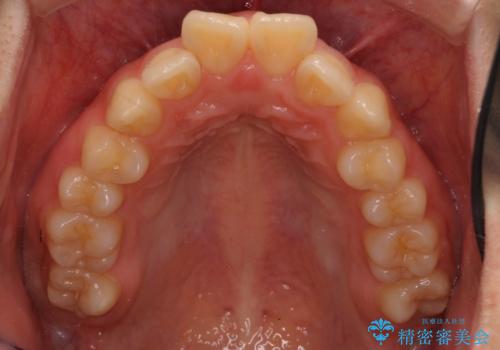

口元を下げたいとのことで、歯を抜いてワイヤー矯正を行いました。

上下左右の小臼歯を抜歯しています。